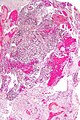

| LM | astrocytic differentiation, nuclear atypia, necrosis, microvascular proliferation, +/-pseudopalisading necrosis |

Microscopic

Features:

- Astrocytic tumour with:

- Nuclear atypia.

- Necrosis.

- Endothelial proliferation (AKA microvascular proliferation).

- +/-"Pseudopalisading necrosis" - tumour cells lined-up like a picket fence around necrotic areas.